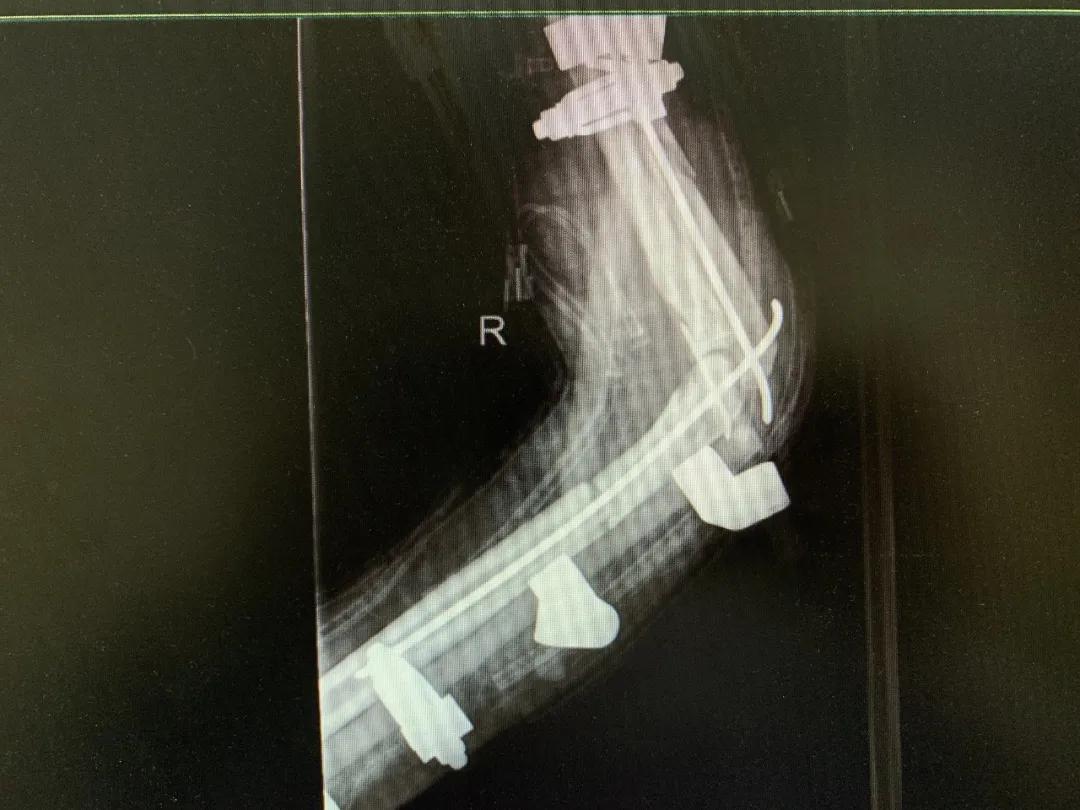

清创、止血、接骨、将粉碎的骨块一块块拼接完整,同时给予VSD敷料负压引流。经过三次清创清除后,明确了坏死的皮肤等组织,创面好转,肉芽组织良好……

“前臂及手指血运缓缓流淌,肢体恢复血供,血运重建获得成功!”次日凌晨4时20分,患者被推出手术室。但是,几次清创后患者前臂皮肤出现大面积缺失,如不及时进行植皮覆盖修复手术,病人极有可能会继发感染,“极有可能造成前臂坏死肢体不保,那么前期所有的治疗和付出也就前功尽弃了。”

经过谨慎讨论,决定取患者左大腿中厚皮片行游离植皮术,以修复前臂缺失的皮肤和肌肉。但这种手术风险很大,要根据前臂缺损的情况,设计从大腿上把需要的皮肤肌肉连同毛细血管一起切取下,再跟前臂的血管吻接才能成活,血管细如发丝,稍有不慎就会导致手术失败,不但上肢保不住还可能给大腿造成继发损伤。